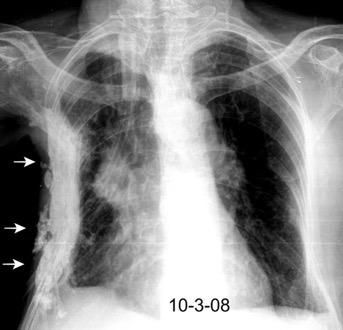

Neumonía a neumococos base izda. con derrame que aumenta.

Broncograma en lateral y en US.

(36-66% en ingresados)